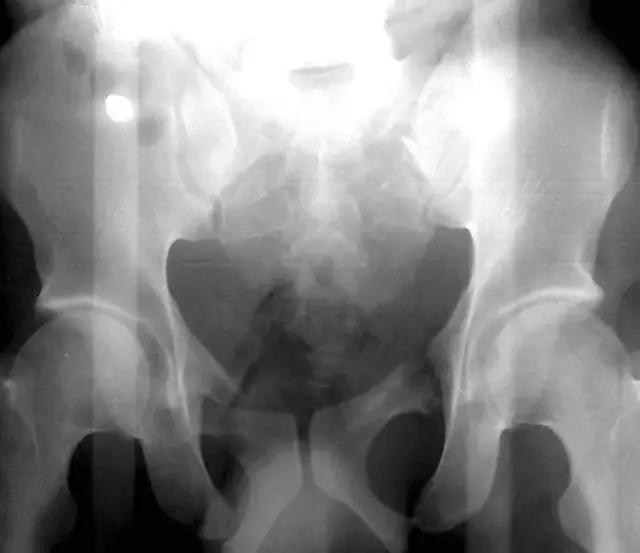

髋膝部骨折

1. Duverney 骨折

髂骨翼的骨折,但没有骨盆环的分离移位。

(来源:radiopaedia)

2. Malgaigne 骨折 (bucket handle 骨折,即桶柄骨折)

不稳定性骨盆骨折伴有前方和后方的骨折线累及髋关节。

3. Straddle 骨折

双侧耻骨上下支骨折。

(来源:learning radiology)